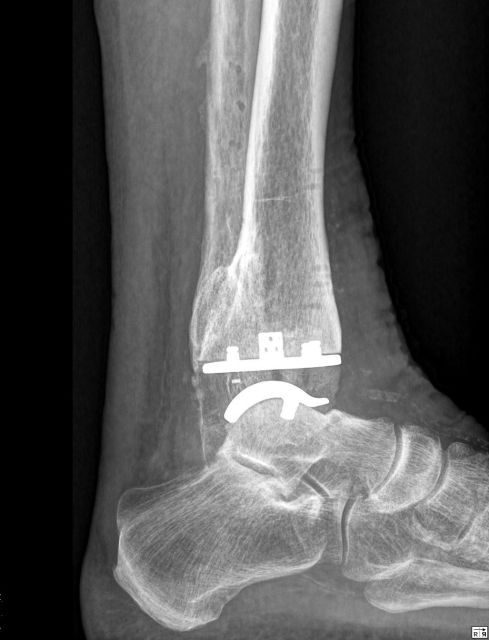

Bei eine Totalendoprothese des Sprunggelenks wird die verschlissene Oberfläche der Knochen mittels Implantaten ersetzt.

Die Verankerung im Knochen erfolgt zementfrei. Der körpereigene Knochen wächst nach einigen Wochen in die Oberflächenstruktur der Prothese ein, sodaß diese mit dem Knochen fix verankert ist. Die eigenen biologischen Bänder des Sprunggelenks bleiben dabei erhalten. Die Operation dauert in erfahrener Hand ca. 2 Stunden. Bis zur Abheilung der Hautwunde sollte nur eine geringe Belastung des Fußes erfolgen. Dabei wird eine Unterschenkelschiene zur Stabilisierung verwendet. Je nach Kraft und Geschicklichkeit benötigt man aus Sicherheitsgründen zwischen 2 und 6 Wochen Krücken zum Gehen. Aufgrund der komplexen Anatomie des Fußes und der häufigen Begleitpathologien sind häufig gleichzeitig noch andere Korrekturen am Fuß notwendig. Ein gleichzeitig bestehender Achsfehler des Fußes wird im Rahmen der Prothesenimplantation mitkorrigiert.

OSG-TP vorher-nachher